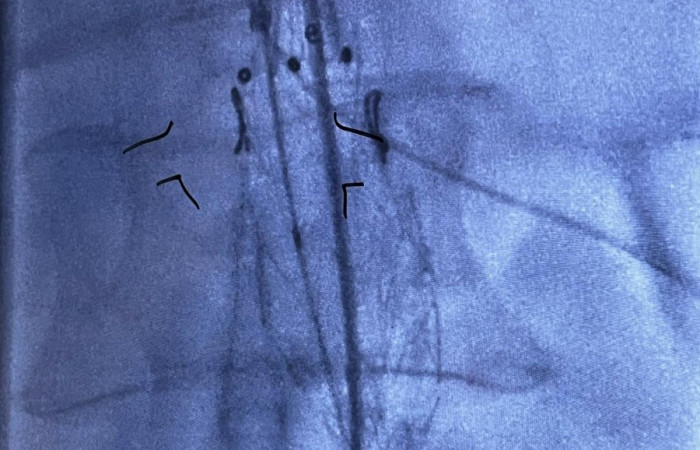

Z dumą dołączamy kolejną innowacyjną metodę do naszego portfolio wysokospecjalistycznych operacji. Wszystko dzięki współpracy pomiędzy Oddziałem Klinicznych Chirurgii Naczyniowej a Pracownią Obrazowania Medycznego 3D przy Zakładzie Diagnostyki Obrazowej NSSU, które umożliwiło postawienie kolejnego kroku naprzód w małoinwazyjnej technice operacyjnej implantacji fenestrowanego stentgraftu do tętniaka aorty brzusznej.

Widoczna na zdjęciach matryca aorty wydrukowana została z żywicy fotopolimerowej, która przeszła proces sterylizacji plazmowej. Użycie technologii 3D umożliwiło indywidualne dostosowanie implantowanego stentgraftu do anatomicznych warunków odejścia naczyń trzewnych od aorty, co z kolei pozwoliło na zakwalifikowanie chorego do małoinwazyjnej procedury zaopatrzenia tętniaka aorty piersiowo brzusznej metodą wewnątrznaczyniową w trybie przyspieszonym.